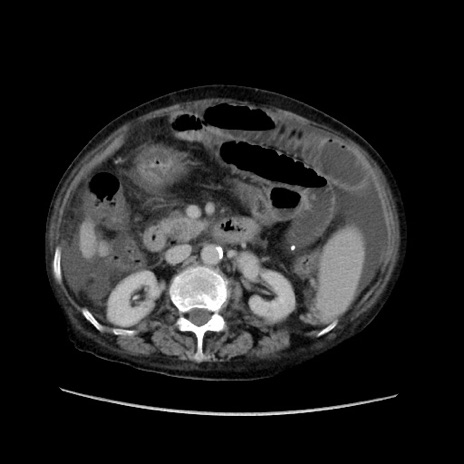

症例31(横断像)

【症例】80歳代 女性

【主訴】腹部膨満感

【現病歴】他院にて肝硬変にてフォロー中。1週間前から便秘、腹部膨満感、臍部腫瘤あり受診となる。

【既往歴】肝硬変

【身体所見】腹部膨隆あり、皮膚変化なし、疼痛なし。

【データ】WBC 4600、CRP 0.25